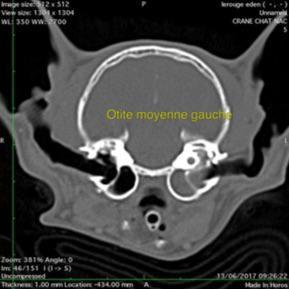

Otite moyenne: bulle tympanique opaque